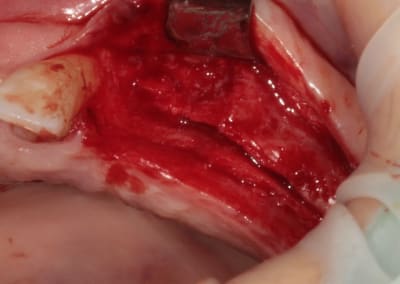

3:

de nouveau ostéotome "lame" angulé

Ostéotome droit, plus étroit que le premier.